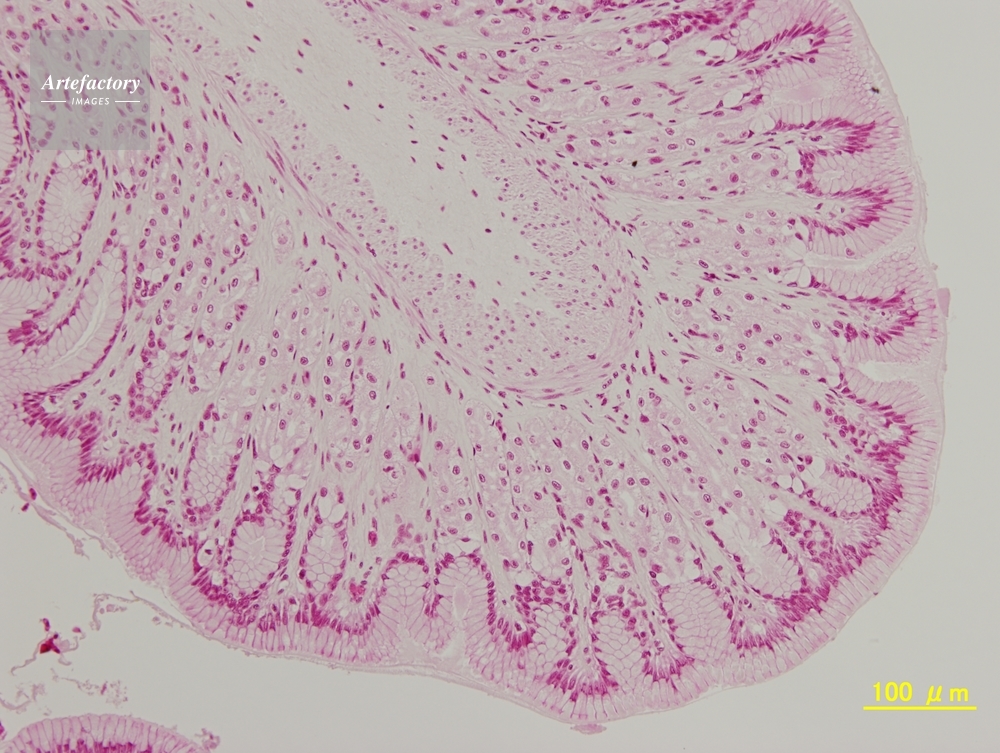

| 作品タイトル | カエル,胃 | モデルリリース | なし | |

| 作家 | OLYMPUS CORPORATION Technolab | プロパティリリース | なし | |

| 撮影年月日 | 2007/6/1 | データサイズ | 5MByte | |